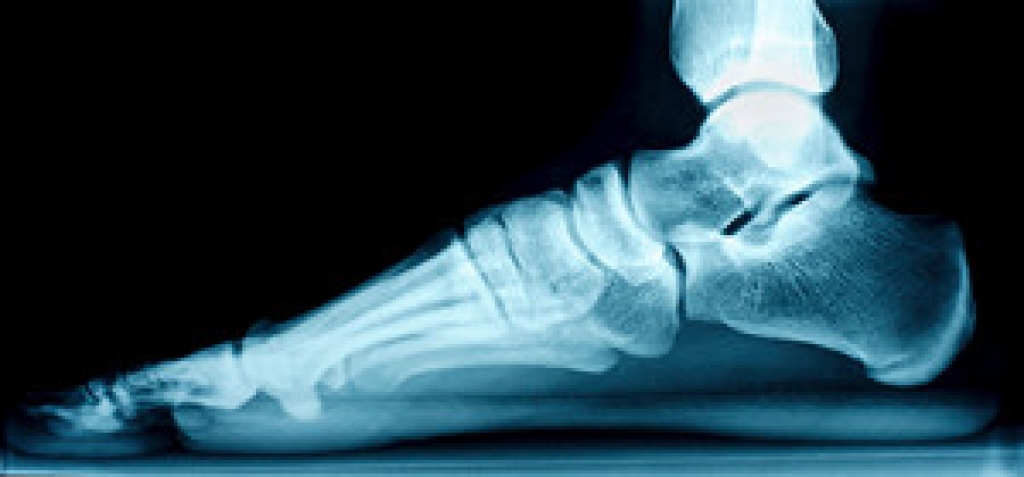

Heel pain is often associated with plantar fasciitis. The plantar fascia is a band of tissues that extends along the bottom of the foot. A rip or tear in this ligament can cause inflammation of the tissue.

Achilles tendonitis is another cause of heel pain. Inflammation of the Achilles tendon will cause pain from fractures and muscle tearing. Lack of flexibility is also another symptom.

Heel spurs are another cause of pain. When the tissues of the plantar fascia undergo a great deal of stress, it can lead to ligament separation from the heel bone, causing heel spurs.